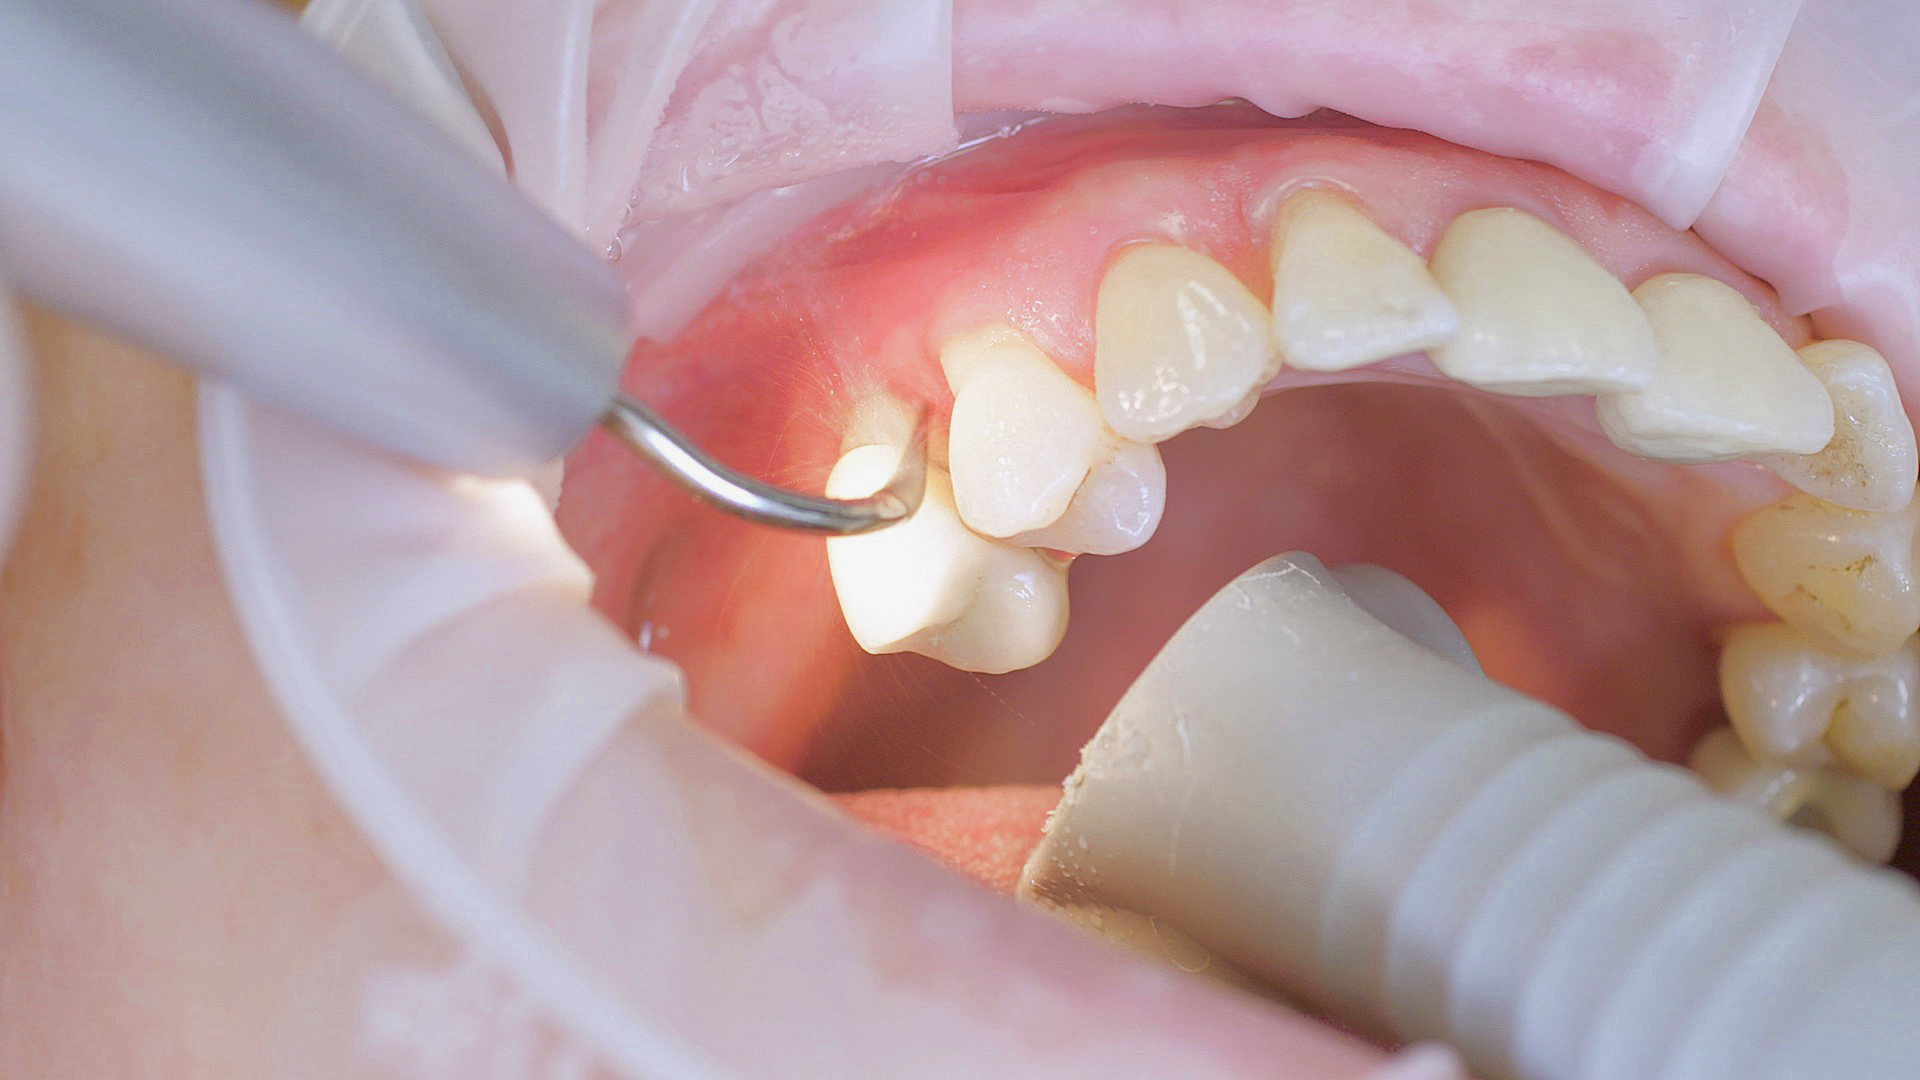

Healthy peri-implant tissue does not show any signs of redness, swelling or bleeding, neither does it secrete pus when probed.[5] Based on the consensus document, Prof. Giovanni Salvi explained the importance of regu- lar probing — preferably with a flexible probe, as implant components often tend to obstruct the procedure.[5] In the case of mucositis or initial peri-implantitis already being present, the non-surgical removal of hard deposits and biofilm should be attempted first. For this purpose, ultra- sonic power and special instruments designed to protect the implant should be employed (Fig. 3; piezo scaler Tigon+ with 1I, W&H). In case of no remission, the recall frequency needs to be increased. However, specific recommendations, applicable to individual cases, are not yet available in this context.[15]